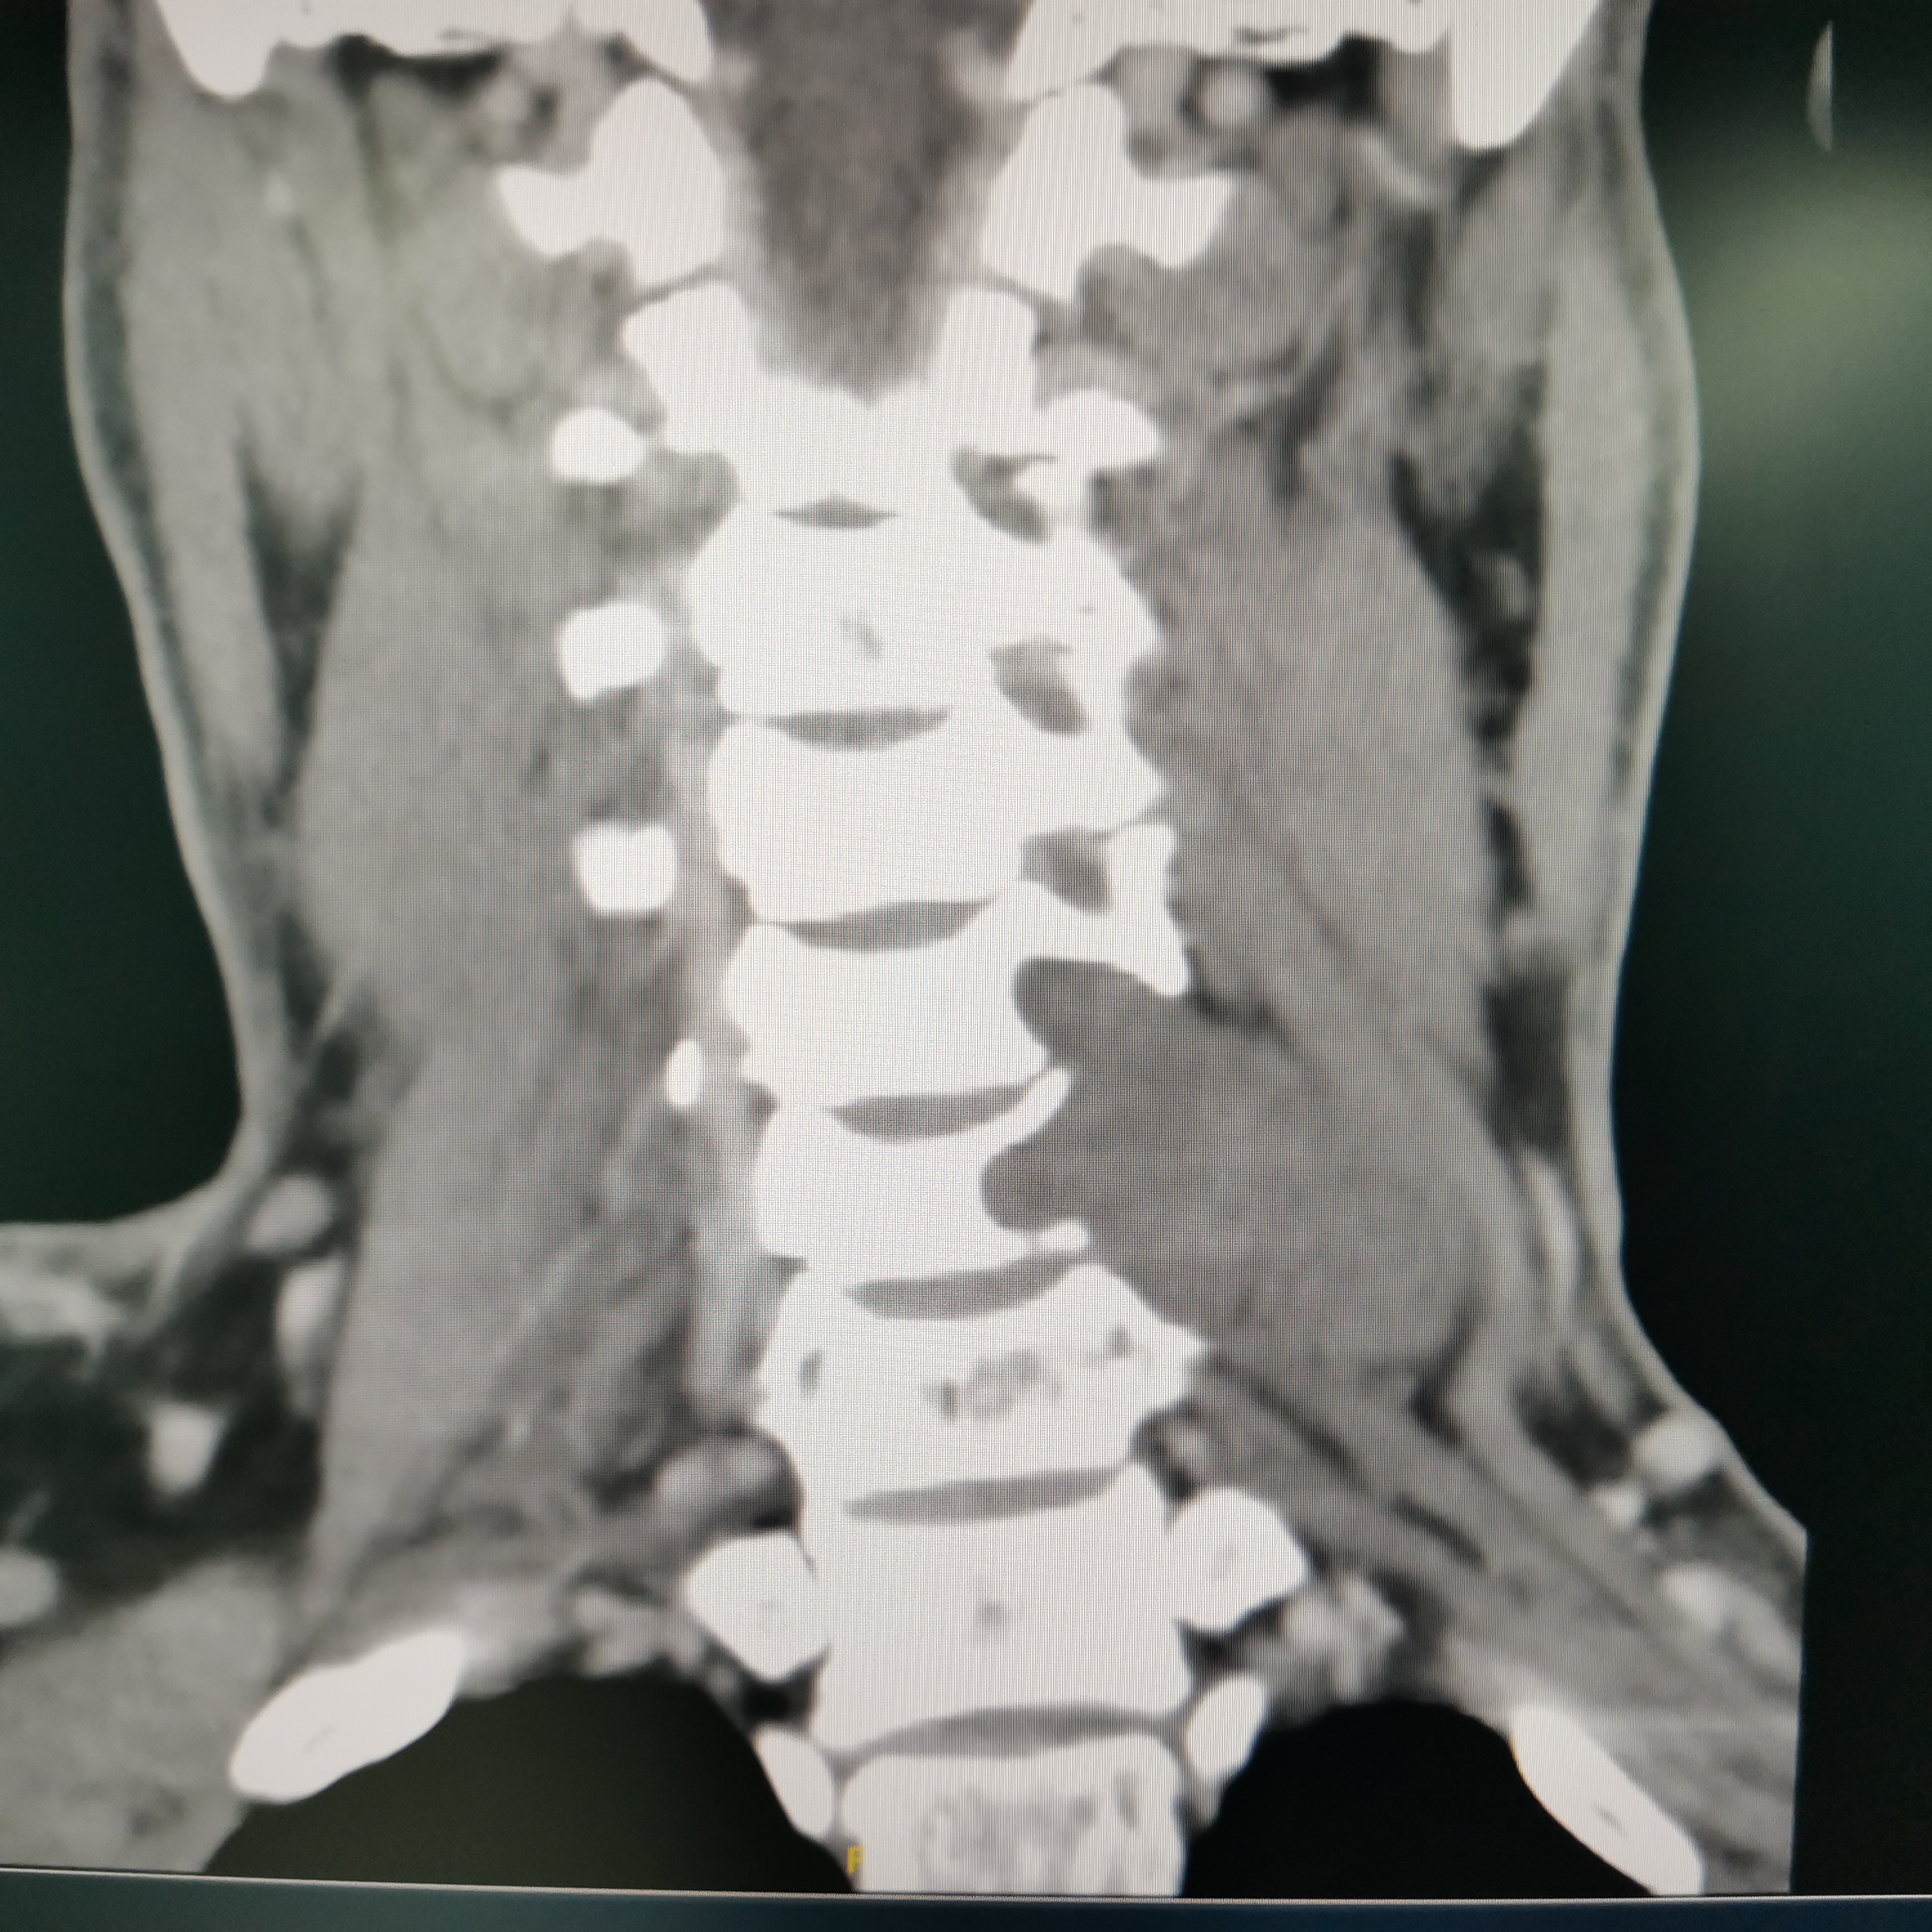

颈椎哑铃型神经纤维瘤,椎间孔汇合,安全又便于操作~